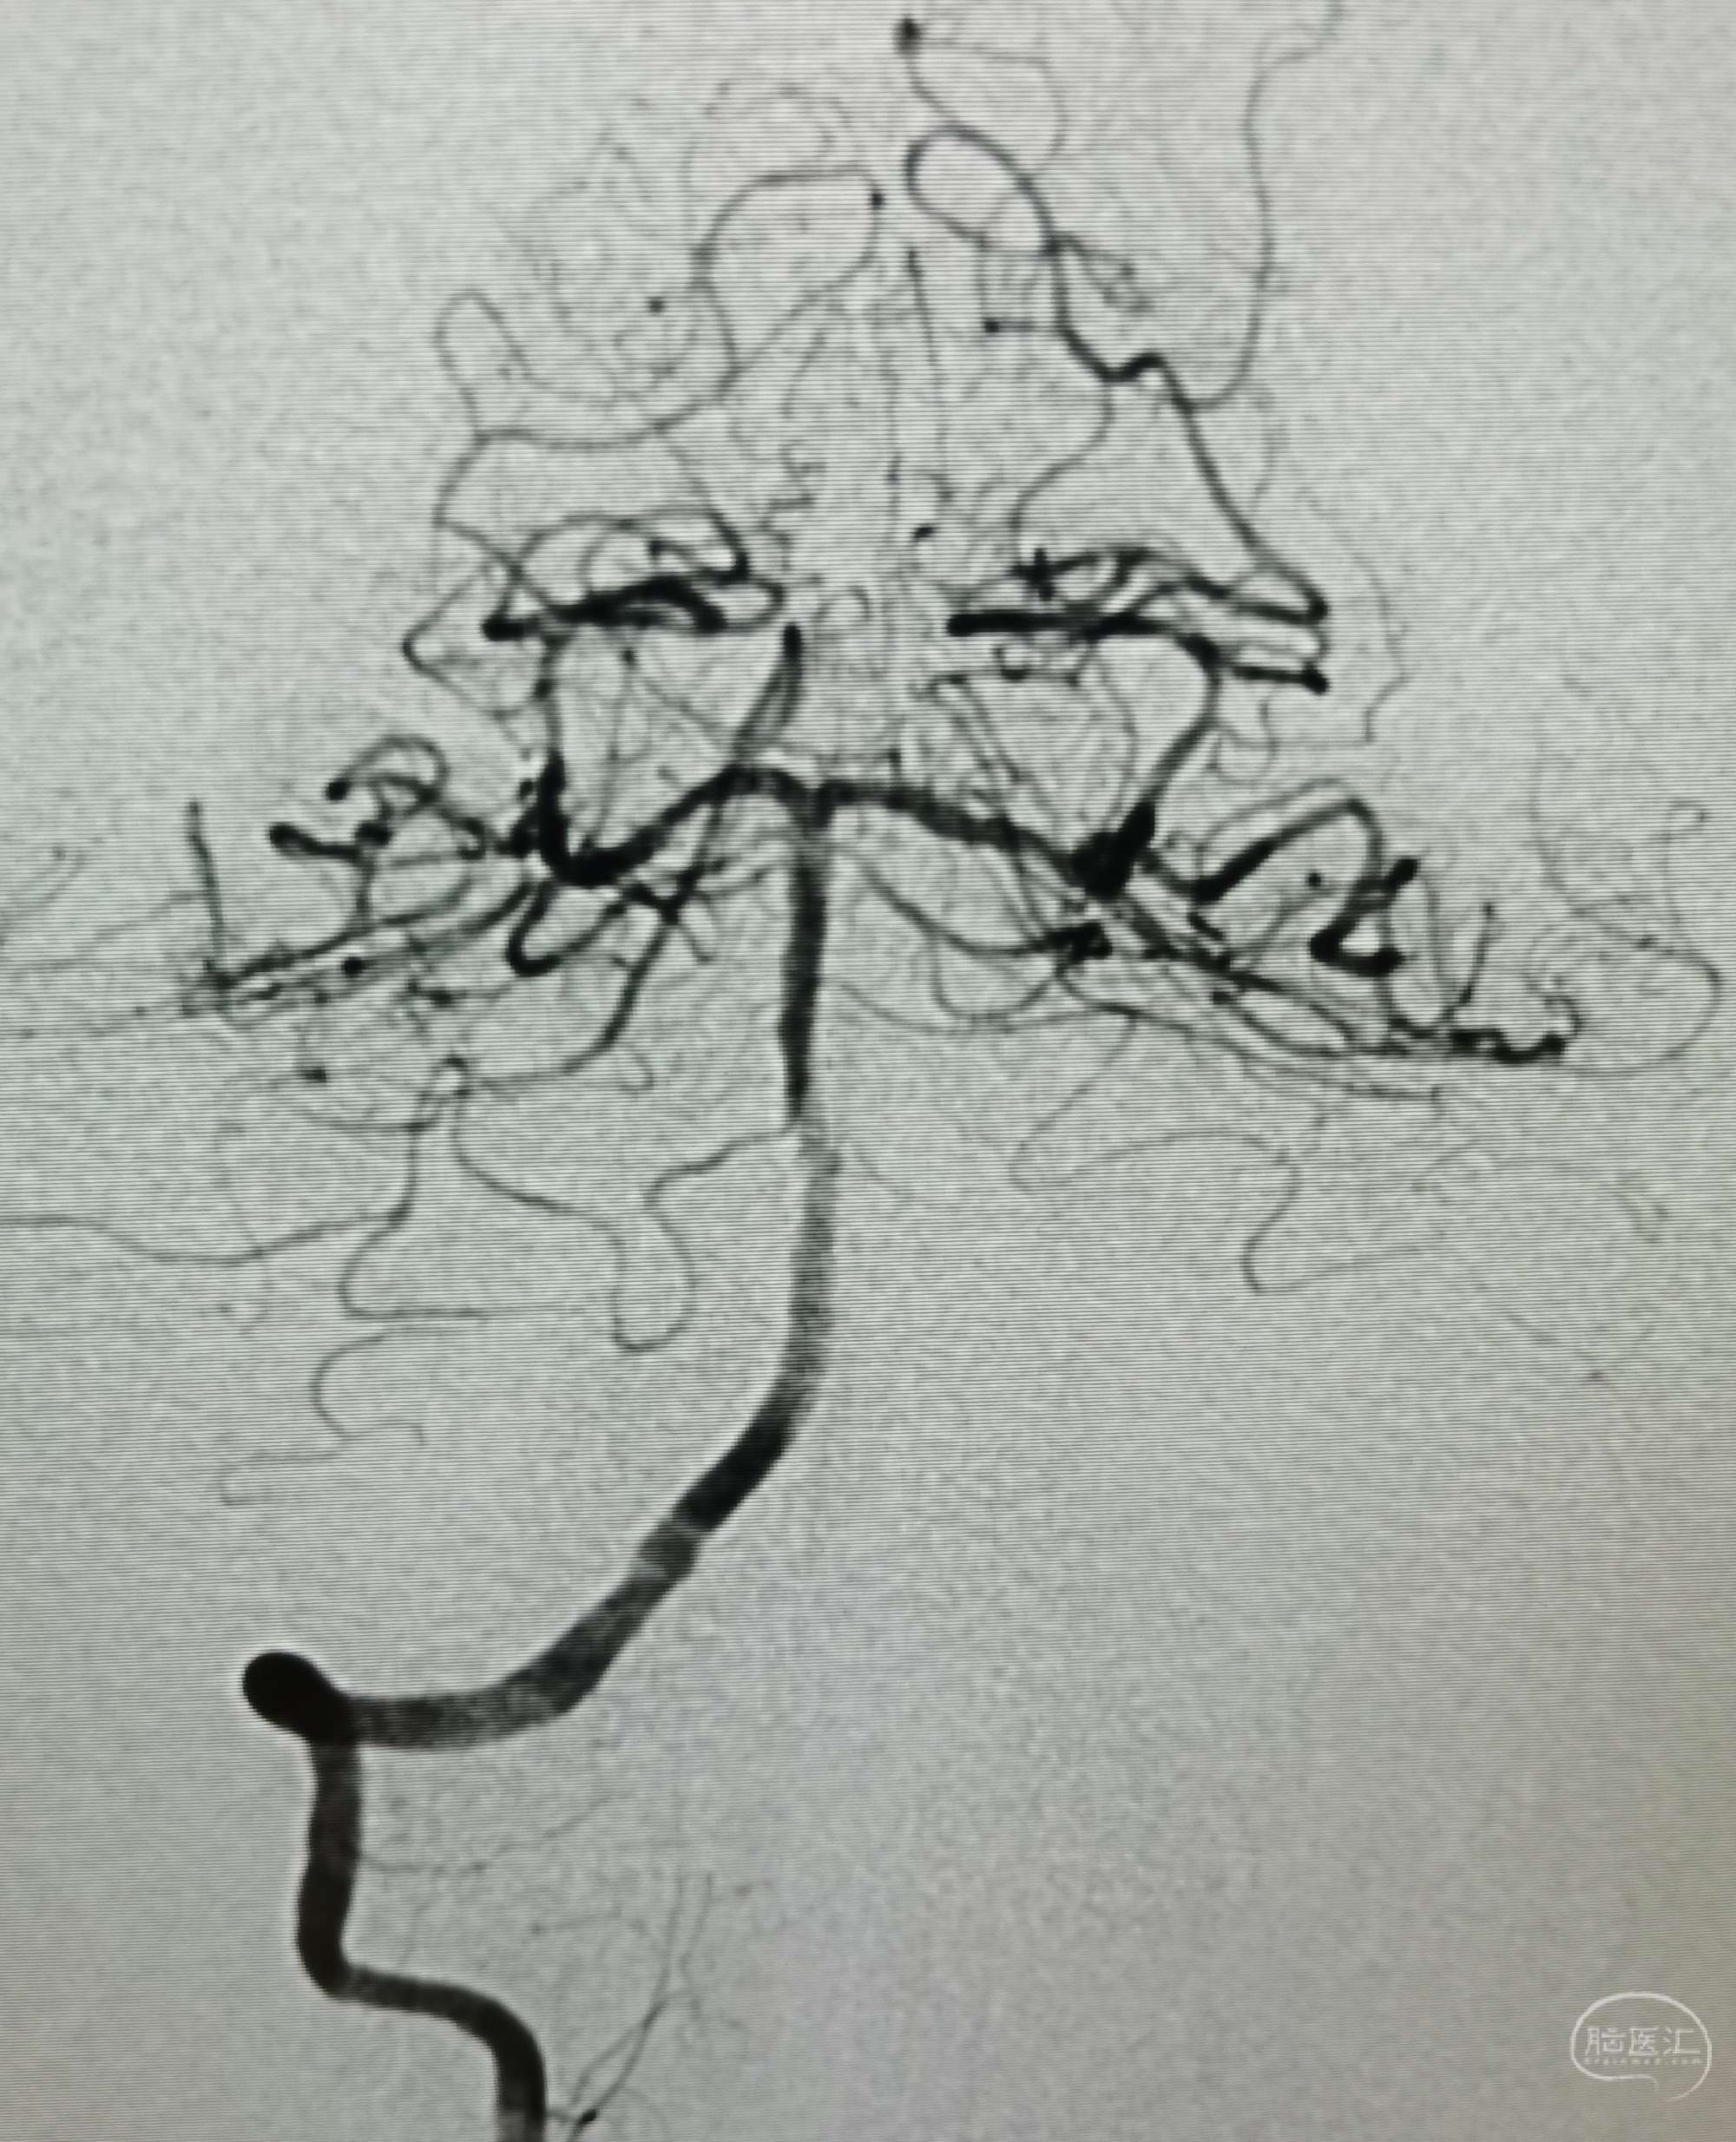

病例5 中年男性,头痛、头晕、记忆力下降一年余。诊断:烟雾病。

脑灌注提示:右侧大脑半球低灌注缺血。

DSA:右侧大脑中动脉、大脑前动脉闭塞,烟雾样血管形成。

颞浅动脉未向颅内代偿。

行颞浅动脉-M4端侧吻合。

颞浅A一只吻合,一只种植。吻合14针。

荧光造影示:吻合桥动脉通畅。